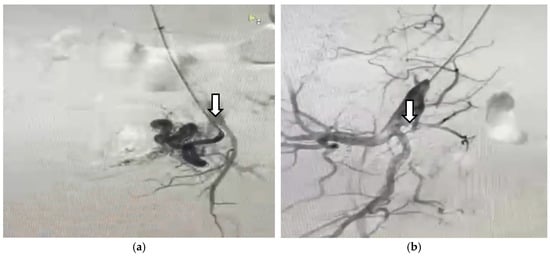

2. Case Presentation